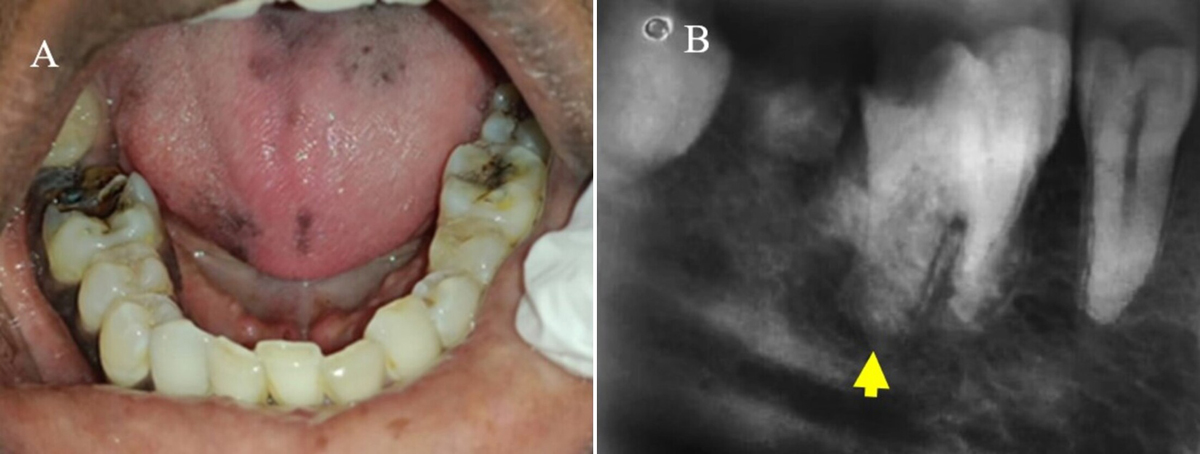

A. Dental caries right mandibular first molar, B. Ill-defined radiolucency in periapical mesial root apex region in right mandibular first molar.